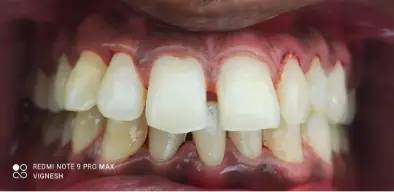

Case 2:

Result 1 Result 1

This young girl had low self-esteem due to the visible gaps in her front teeth. This affected her smile and oral hygiene as well. Therefore, she was suggested Illusion Aligners by her dentist. Illusion Aligners shifted her teeth in the ideal position, closing the gaps. The patient was very happy and satisfied with the results.